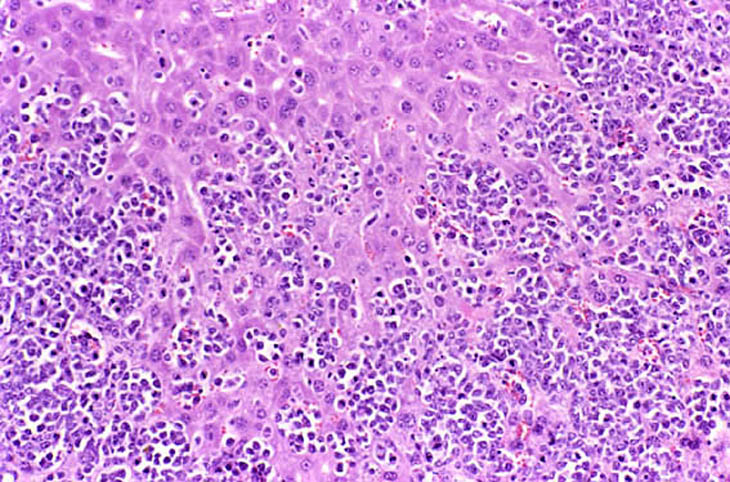

The liver is a relatively frequent site of infiltration by malignant lymphocytes, especially in strains with a high prevalence of lymphoma.

Infiltration of malignant lymphocytes in a liver from an adult mouse.

Severe infiltration of the liver by malignant lymphocytes. Hepatocytes visible in the lower right corner.